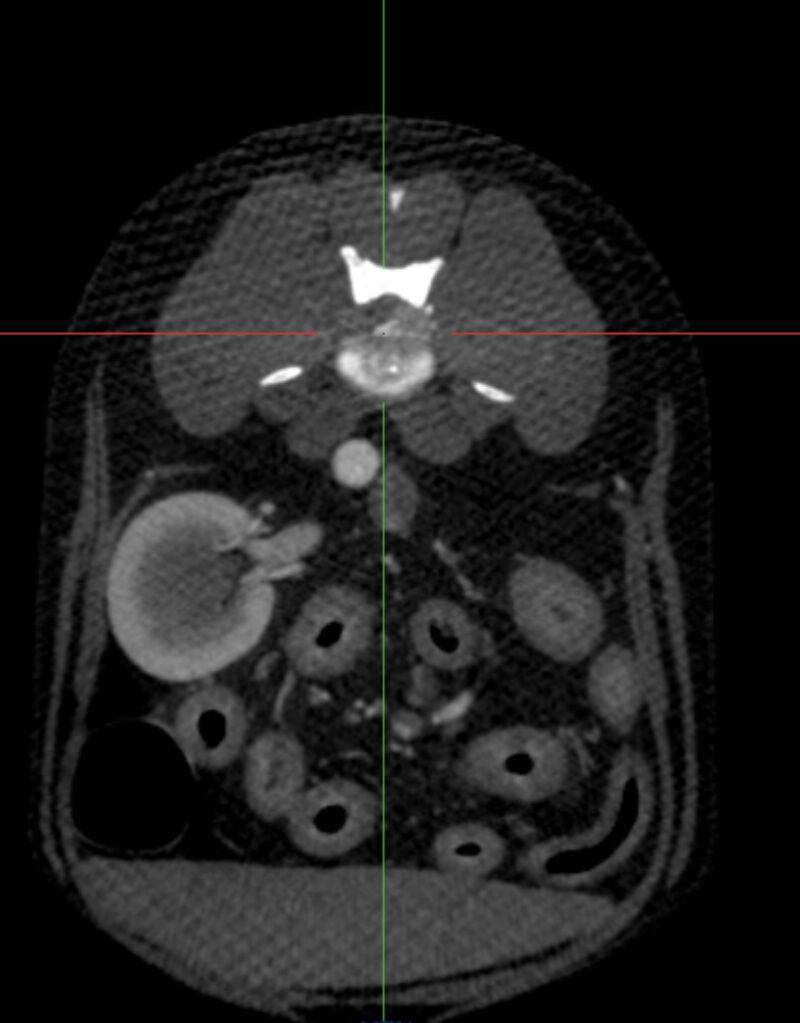

Abdomen: Ein wesentlicher Schwerpunkt unserer klinischen Arbeit liegt im Abdomen. Neben der Darstellung abdominaler Tumoren und struktureller Organveränderungen konnten auch Gefäßanomalien wie portosystemische Shunts erfolgreich dargestellt werden. Für viele klar definierte Fragestellungen stellt das CBCT eine praktikable und diagnostisch wertvolle Alternative zum MSCT dar (Abb. 5 & 6).